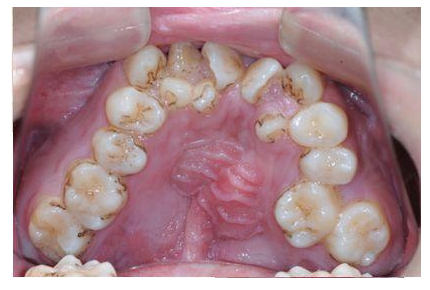

牙齿畸形不仅影响美观,还可能会影响口腔功能的正常发挥,如咀嚼功能、发音功能、呼吸功能,甚至由于牙齿排列不齐,难以清洁导致蛀牙等。

对于青少年阶段的牙齿畸形问题,应该及时选择适宜的早期矫治,才能更好地促进儿童面部和牙弓的发育,为现有牙齿和即将萌出的恒牙创造空间。